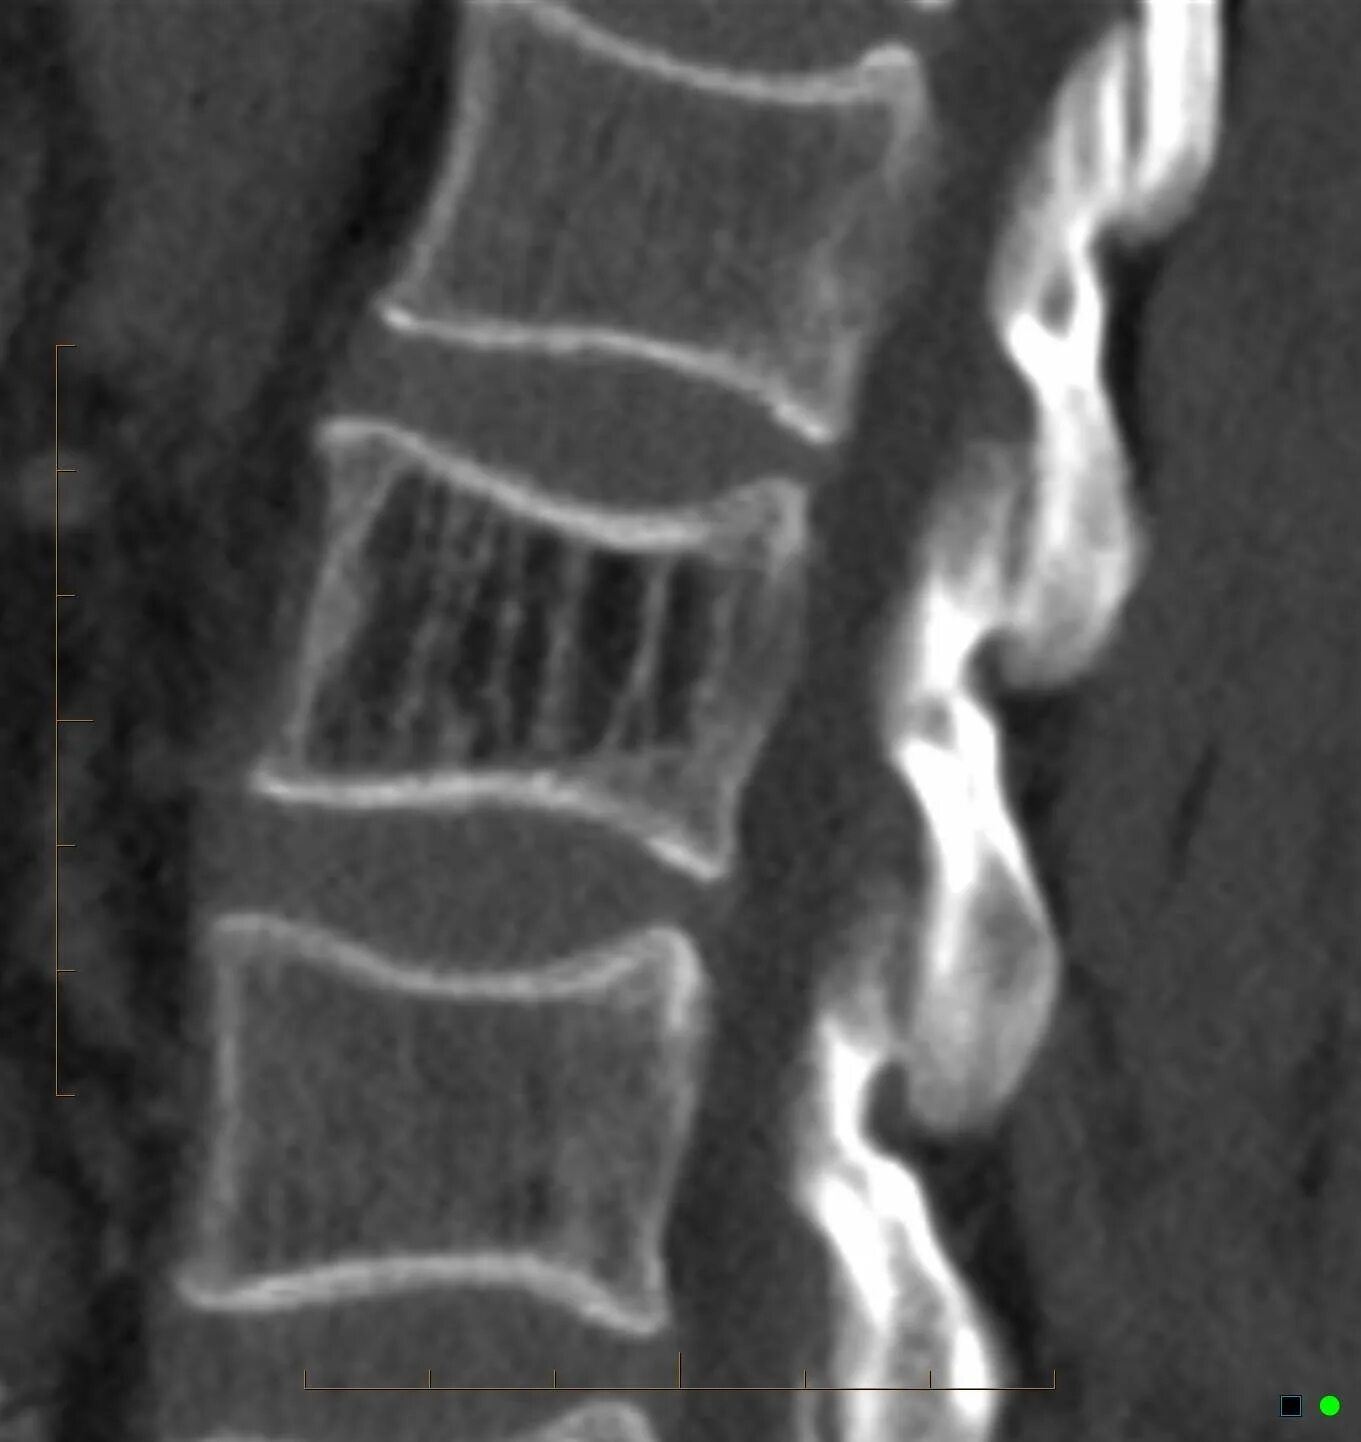

Гемангиомы позвонков шейного отдела